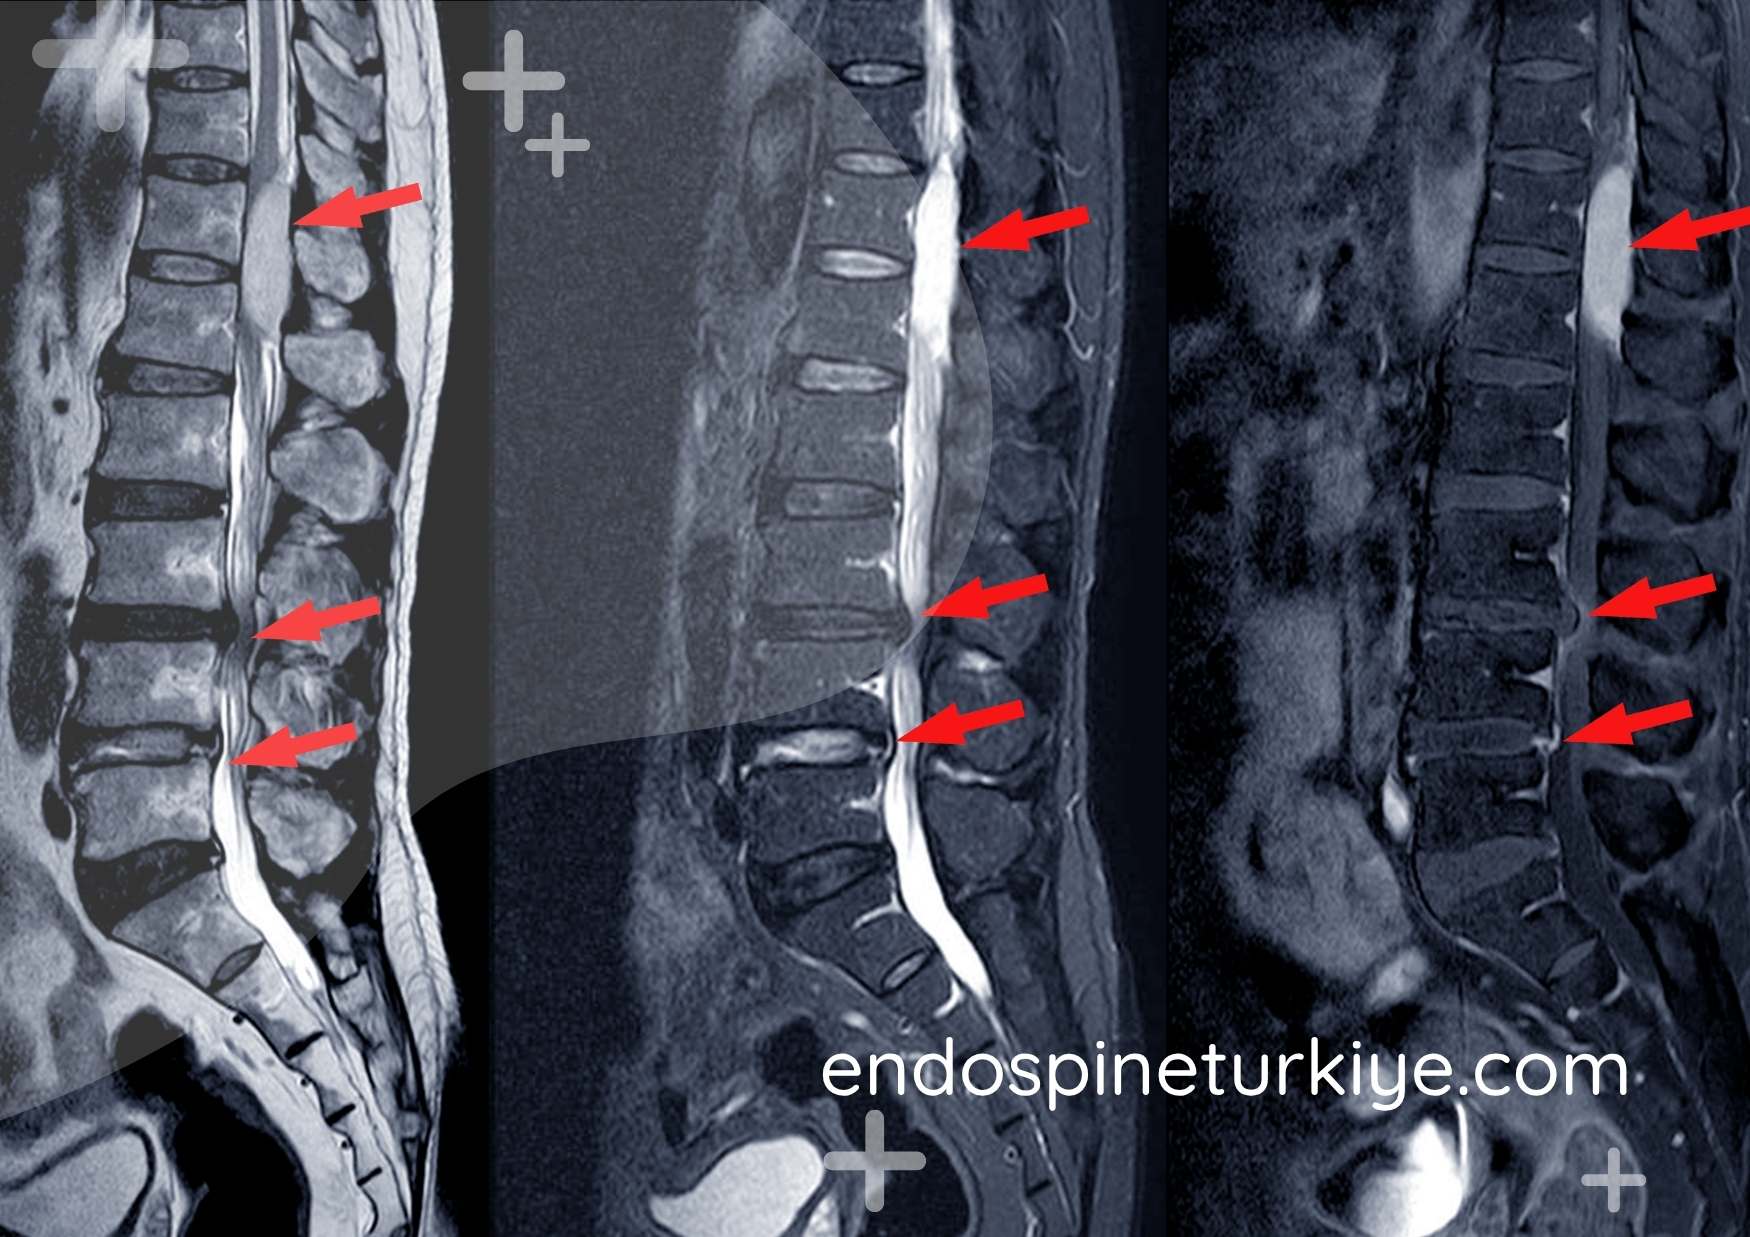

Tam Kapalı Dar Kanal Ameliyatı Öncesi ve Sonrası

Tam kapalı dar kanal ameliyatı öncesi MR - kanal darlığı görüntüsü Ameliyat Öncesi

Tam kapalı endoskopik dar kanal ameliyatı sonrası MR - dekompresyon sonucu Ameliyat Sonrası